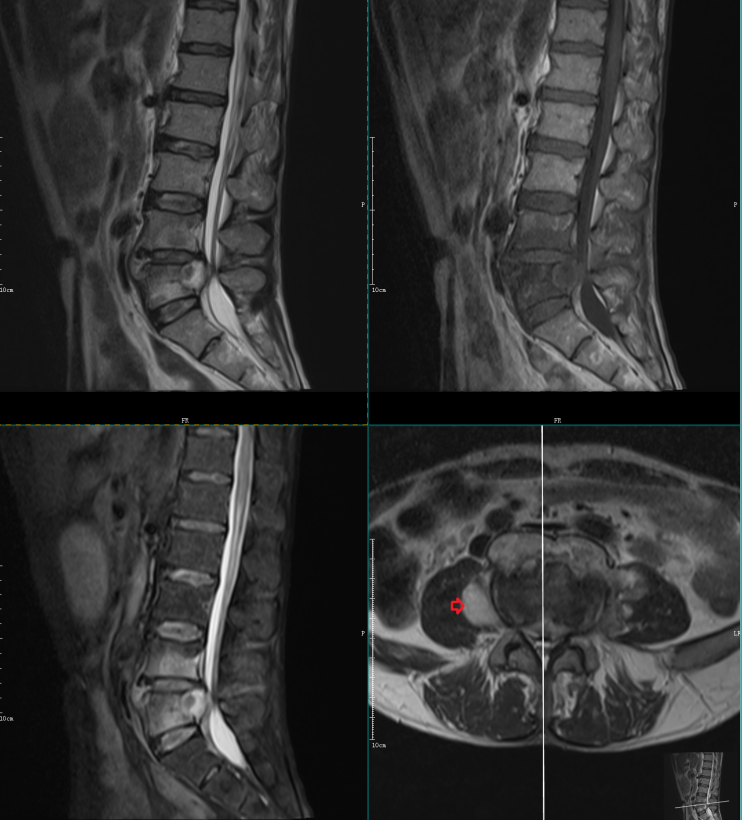

转移瘤:有肿瘤病史,病变很少累及椎间盘,多个椎体溶骨性或膨胀性破坏,肿瘤易侵犯附件、椎管或椎旁。

MRI示 部分椎体及附件信号异常,T1WI及T2WI呈低信号,STIR序列呈明显高信号,DWI序列呈高信号。考虑为转移瘤。